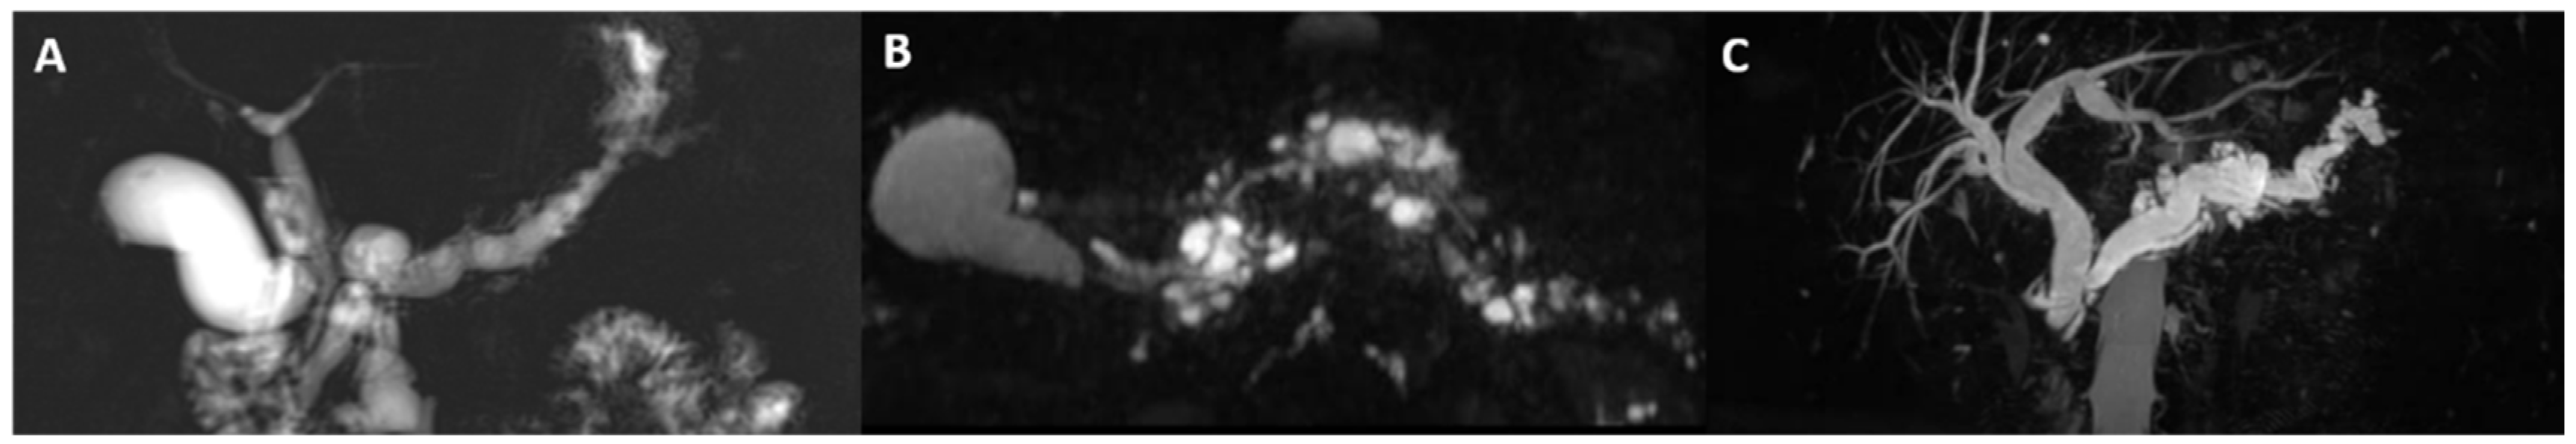

:1. Introduction